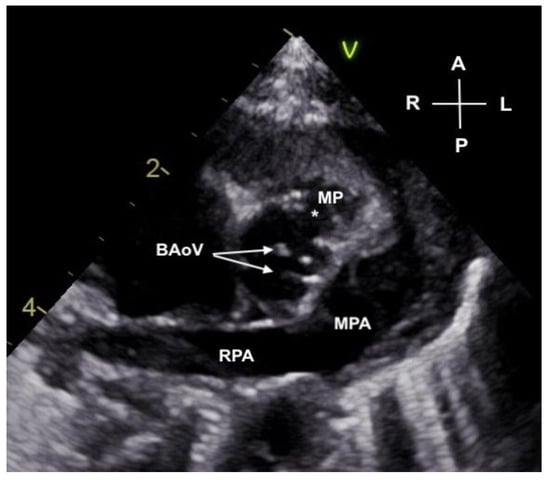

Figure 3.

Parasternal short axis view of the bicuspid aortic valve (BAoV) with valve leaflets noted by arrows. A deficiency in the anterior sinus of Valsalva (*) has “mined” a cavity into the surrounding myocardium creating a pouch (MP).